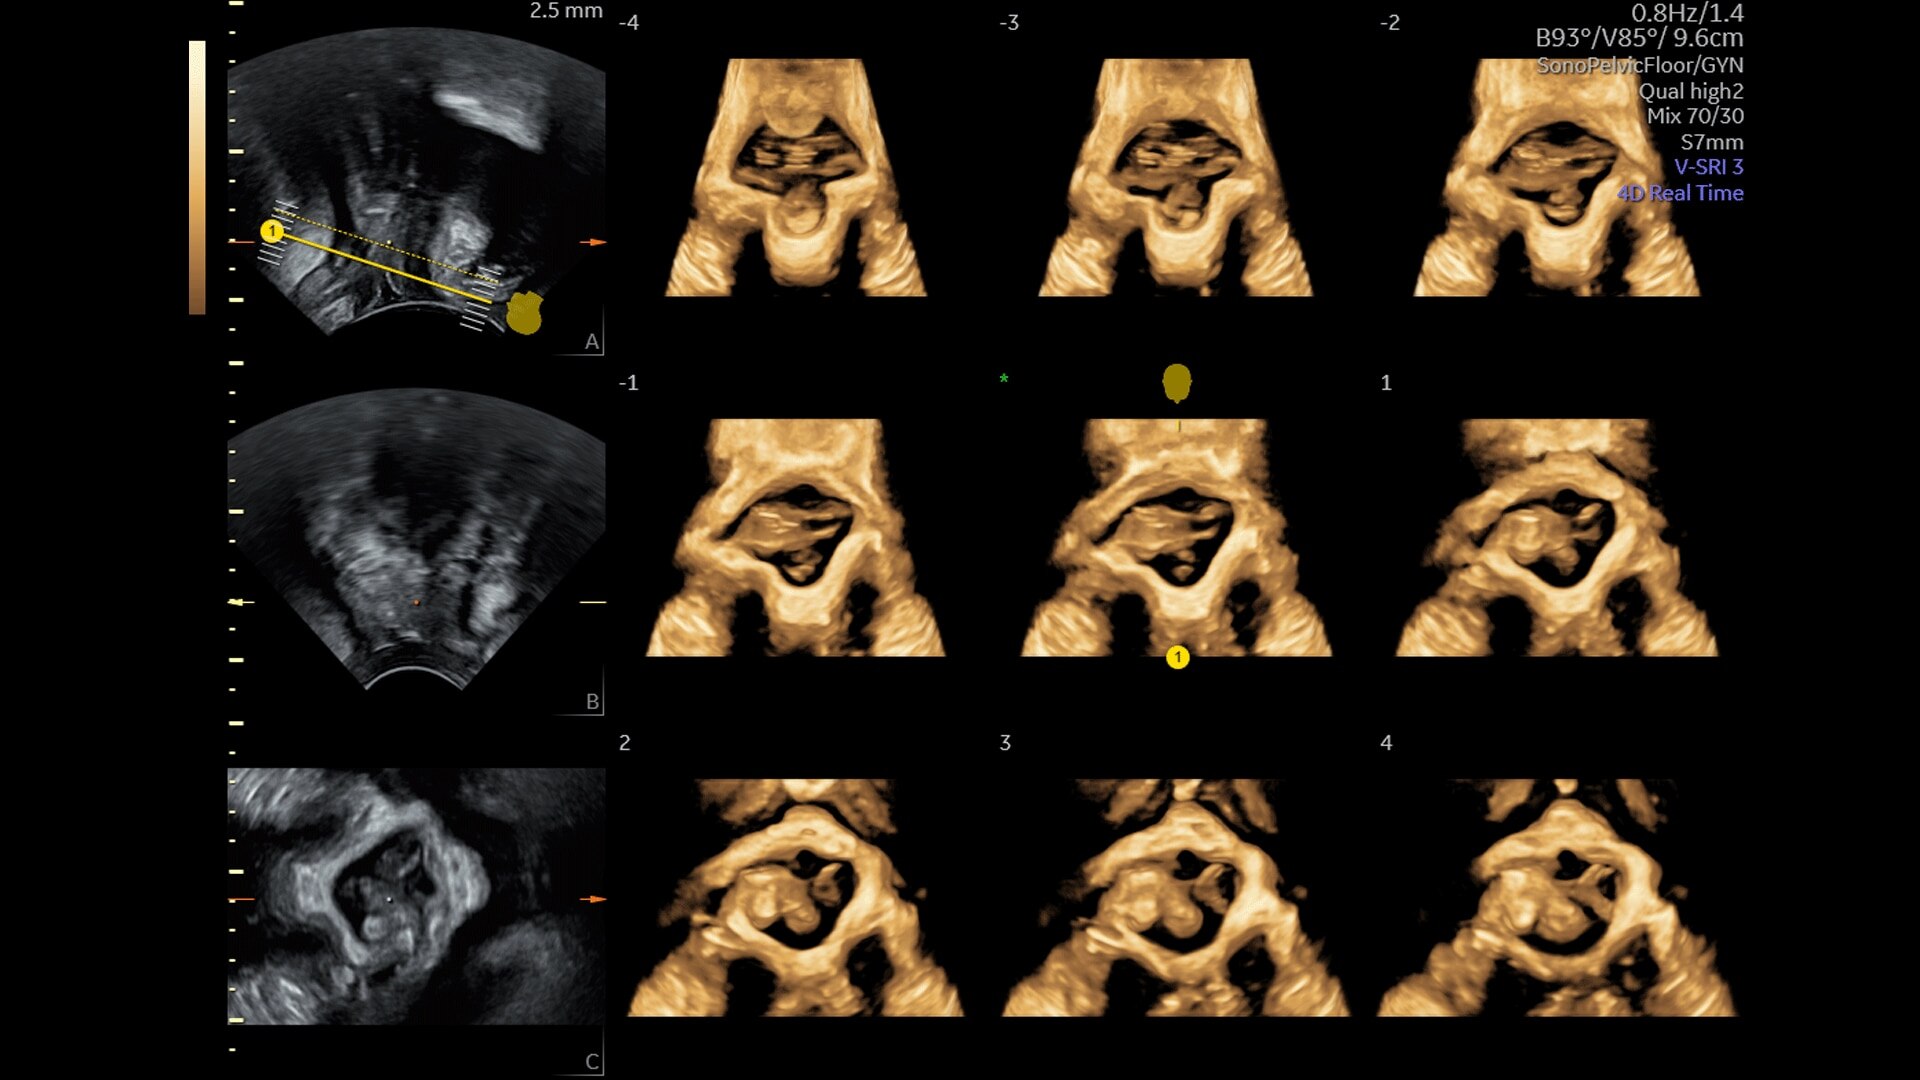

Generate spectacular 2D/3D and color Doppler images with increased penetration and stunning clarity, to help visualize critical details needed for diagnostic assurance. The Lyric Architecture unlocks new imaging and processing power to expand your imaging capabilities for years to come

Experience a new level of efficiency with the highly intuitive and customizable ultrasound that promotes progress and productivity. Leverage the power of artificial intelligence and easy-to-use automation tools that streamline workflows and make a real impact every day.